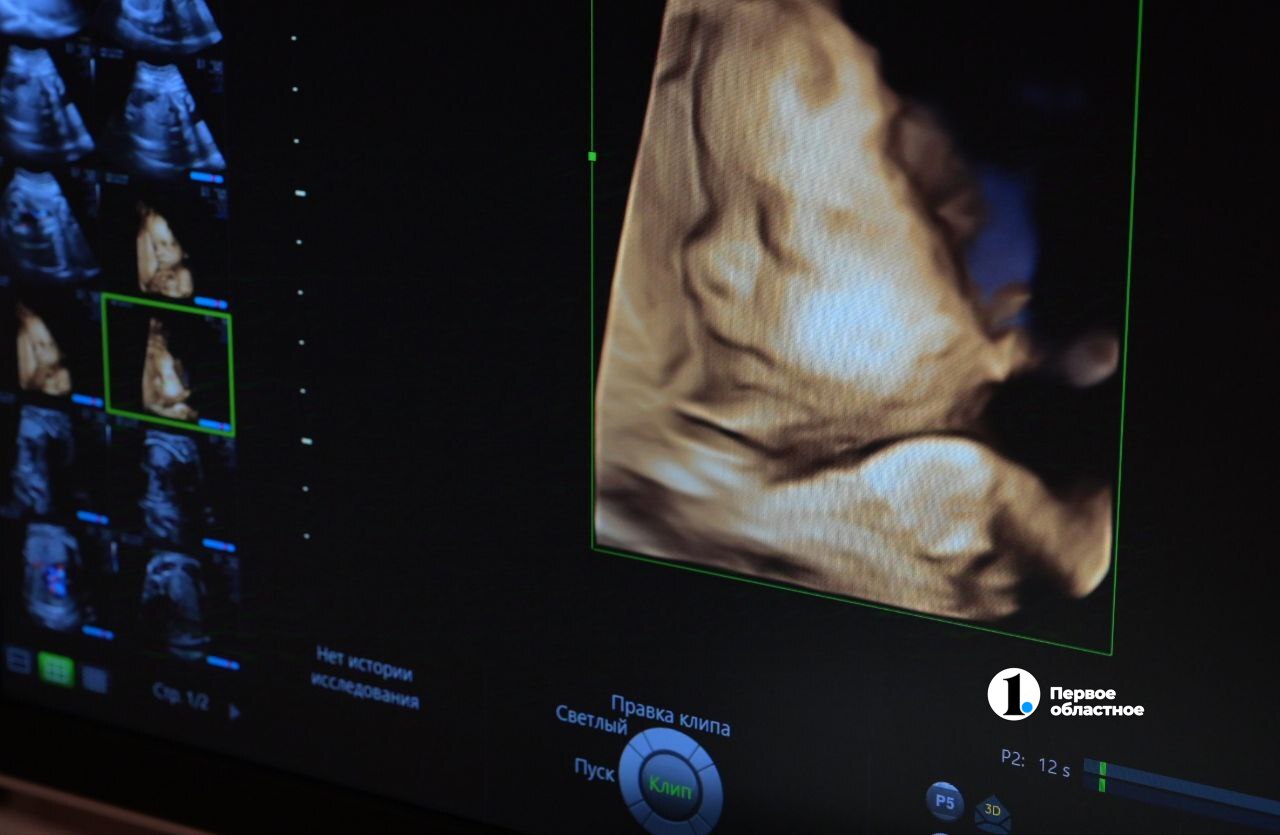

Свою профессию доктор считает самой необычной и захватывающей дух, ведь именно врач УЗИ видит, как зарождается новая жизнь, что похоже на чудо.

«Прежде всего, развиваются и растут. Некоторые детки очень спокойные — во время УЗИ они спят. Другие шевелятся, они активные. Благодаря современным технологиям мы можем увидеть, как они улыбаются, сосут пальцы, ловят ручками свои ножки, облизывают плаценту, играют с пуповиной, крутятся, вертятся, плавают. То есть делают абсолютно весь спектр движений, которые может совершать человек. Хотя удивительно: после рождения они лежат и даже не могут самостоятельно повернуться», — рассказывает Мария Токарева.